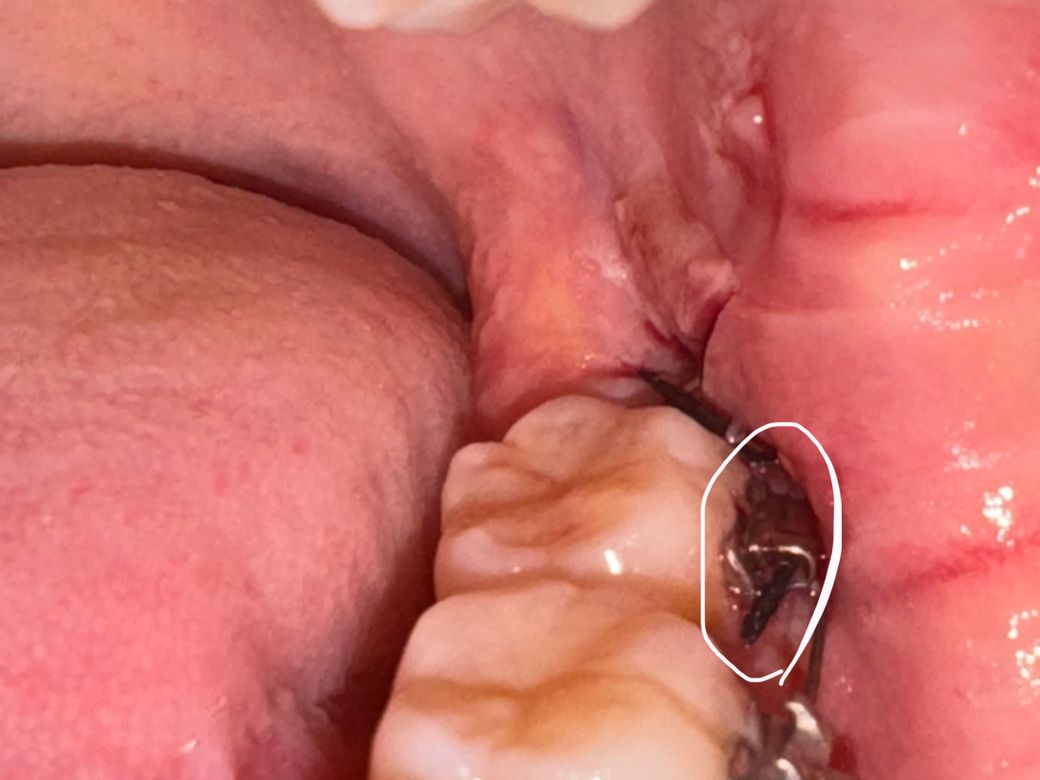

목요일 저녁에 사랑니 발치했습니다갑자기 뭔가 이물감이 들어서 음식물이 낀줄알고 거울로 보니 실빱이 교정기에 끼어있습니다..이게 실빱이 풀려서 낀건지 아니면 실빱이 길어서 낀건지 모르겠습니다 크게 아프진않은데 뭔가 불편하네요 괜찮은건가요? 얼굴이 부어서 안쪽까지 잘 보이지도 않고..병원에 가야할까요

그냥두면 됩니다. 아마도 교정지 틈새로 봉합 것으로 보입니다. 교정기 때문에 교정기 옆이나 밑으로 봉합하는 경우 종종 발생합니다.

실밥이 좀 풀려버린 것 같습니다 지혈 잘 되었다면 큰 문제는 없을 것 같습니다 불편하다면 치과가보시고 아니면 그냥 약속된 실밥 푸는날 내원하세요

잇몸에 봉합해놓은 실밥이 교정기 위에 넘어와잇는거 같습니다. 실밥을 제거하면 사라지니 너무 걱정하지마세요.